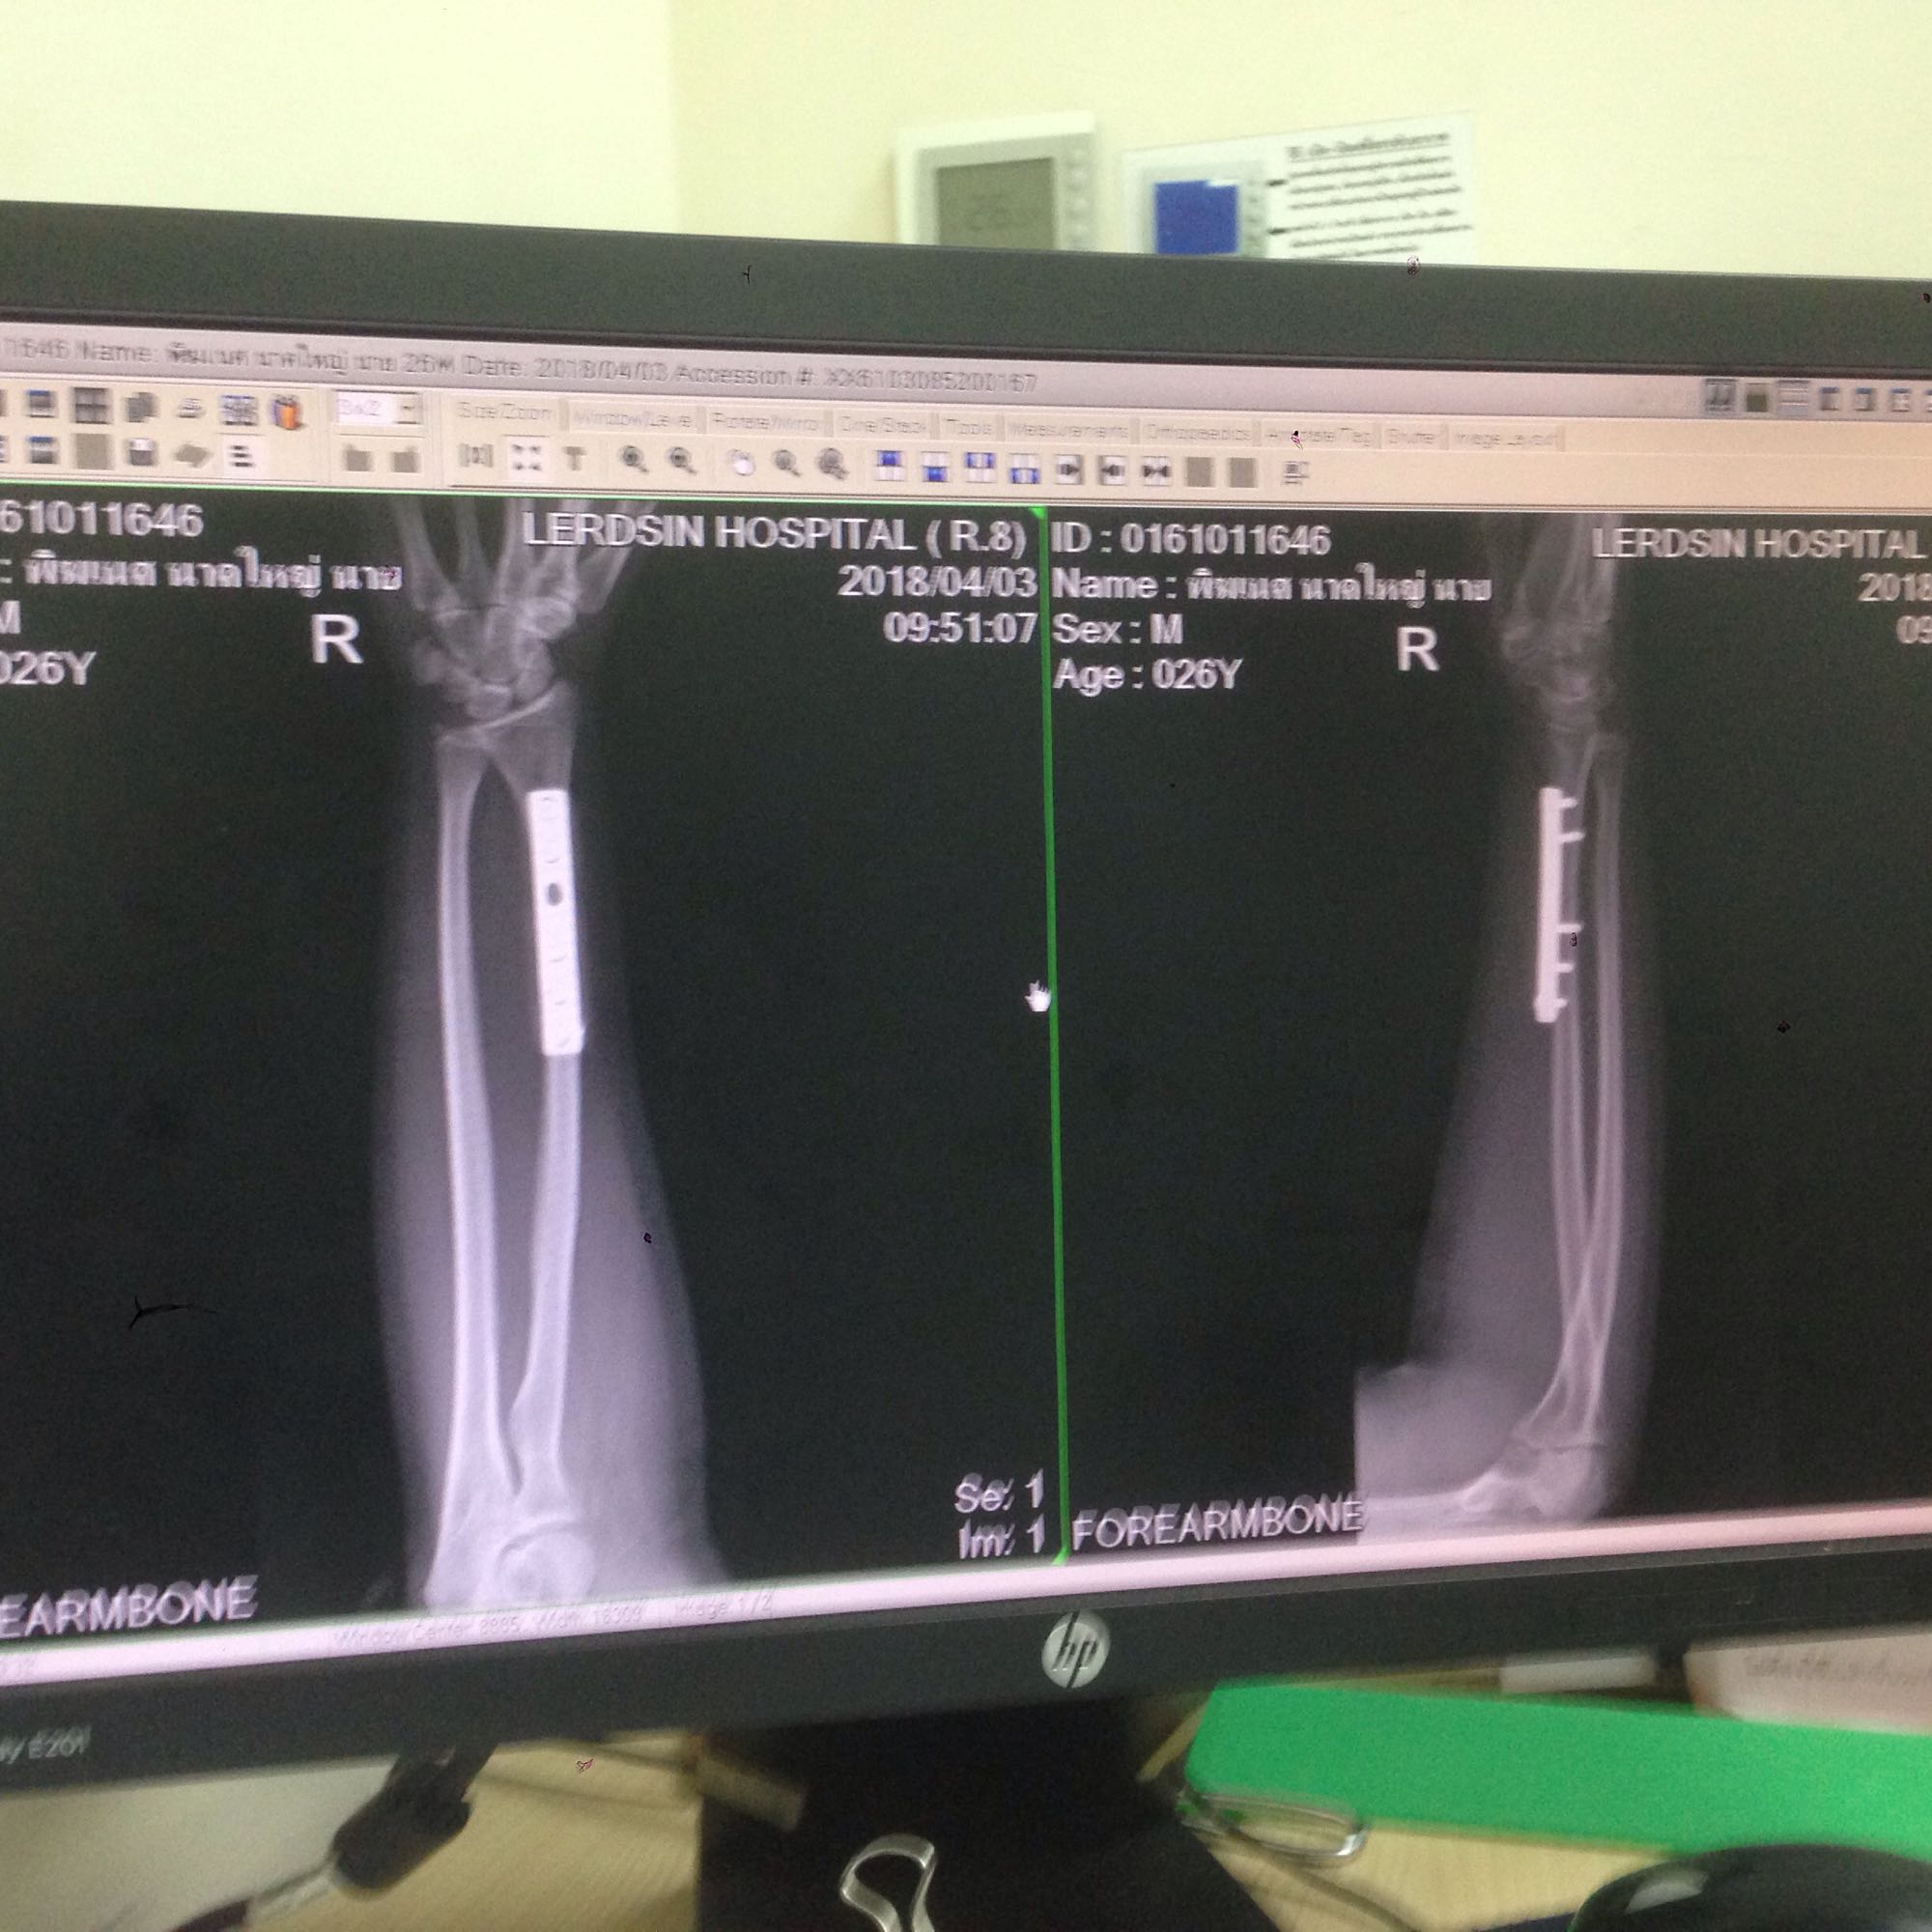

นี่รูปเหล็กในแขนครับ

เรื่องเกิดเมื่อวันที่2มี.ค.ที่ผ่านมา  รถแท็กซี่รอเลี้ยวข้ามสะพานเข้าซอยด้านข้างเตาปูนแมนชั่น  ผมขับมอไซค์มาทางหลังปกติ  เห็นในระยะ1-200เมตรได้ว่ารถรอเลี้ยว  เพราะหน้าผมไม่มีรถเลย  แต่เขาไม่ยอมเลี้ยว  ตอนแรกผมก็ชะลอดูว่าเขาจะเลี้ยวมั้ย  แต่เขาเหมือนจะรอผมไปก่อน  แล้วพอระยะห่างได้ไม่ถึง5เมตรผมเลยเร่งเครื่องเพื่อจะรีบผ่านไปให้เขาเลี้ยว      แต่ในจังหวะที่กำลังจะผ่านเขาตัดสินใจเลี้ยวรถตัดหน้าทำให้เบรคไม่ทัน แล้วชนเข้าที่ด้านข้างของท้ายรถเขา  ทำให้ผมแขนหักค้องผ่าตัดเพื่อใส่เหล็กที่กระดูกแขนขวาข้างถนัด แผมไปใช้ประกันสังคมที่โรงบาลเลิดสิน และเป็นช่วงที่ผมทดลองงานยังไม่ผ่านโปร ทำให้ผมต้องออกมารักษาตัว พอผมบอกประกันว่าต้องออกจากงานมารักษาตัว  เขารีบบอกว่าเขาจ่ายค่าชดเชยต่างๆให้ผมเป็นคิดวันละ300-500ตลอดเวลาการรักษาตัวหักเสาร์อาทิตย์ด้วย  พอผมมาคิดๆแล้วถ้า2เดือนผมได้แค่2หมื่นเอง   ซึ่งมันทุเรศมากเลยครับ ผมจะกลับมาทำงานได้เหมือนเดิมหรือใช้แขนได้ดีเท่าเดิมรึเปล่าก็ไม่รู้  ใครพอจะแนะนำอะไรหรือวิธีสู้กับประกันให้มั่งได้มั้ยครับ  ผมไม่ค่อยรู้เรื่องพวกนี้เท่าไหร่ พรุ่งนี้ไปคุยกะประกัน เรื่องมันช้ามากเพราะเขาให้ผมไปเอาเอกสารที่รับรองว่าผมเป็นพนักงานมาและเงินเดือนที่ได้ด้วย เขาบอกจะเอามาดูว่าผมได้เงินเดือนเท่าไหร่จะได้จ่ายชดเชยรายวันได้ถูก  ซึ่งผมมีแค่ใบลาออก ขอHRแล้วเขาไม่ทำให้  ผมก็งงตรงที่มันต้องใช้ด้วยเหรอ  ปล.ผมอายุ26ทำงานเขียนแบบและออกแบบ